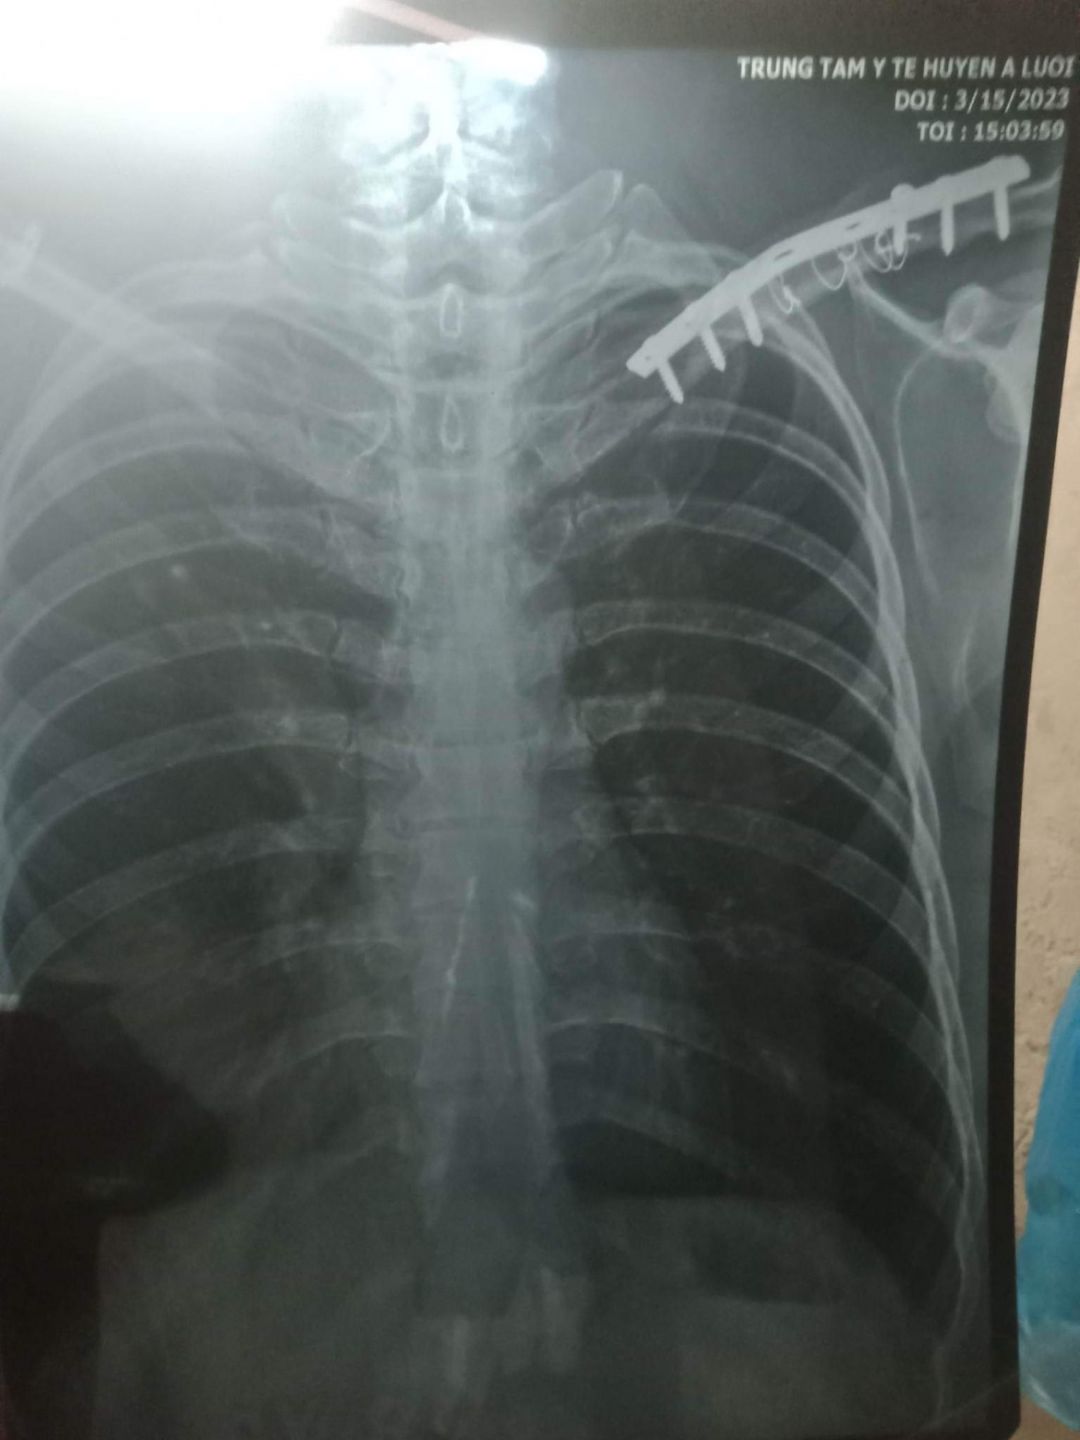

3. Hồ sơ chụp phim có ạ ( em up đính kèm ảnh ạ

4. Giảm khi tháo ốc vít: Khó báo số tiền chính xác ạ, thường thì thuốc ngoài bhyt chi phí nhiều , phí mổ cũng nằm ngoài bhyt ạ. Ra viện thì được thanh toán gần 45 nghìn đồng/1 ngày nhưng hiện không biết nếu mổ thì nằm bao nhiêu ngày ạ( em có up ảnh sdt khoa chấn thương

Em xin thông tin hoàn cảnh của HS Nguyễn Thị Thu Hương. Bố và mẹ em ly hôn từ năm 2019, bố tên là Nguyễn Văn Dũng 38 tuổi. Nghề nghiệp tự do. Thu nhập trung bình một tháng từ 1.5 đến 2 triệu, phụ thuộc vào thời tiết và sức khoẻ. Một mình bố nuôi hai con đang ăn học. Con gái đầu tên là Nguyễn Thị Thu Hương 18 tuổi đang học lớp 12. Con gái thứ hai tên là Nguyễn Hoài Thu Hà, 15 tuổi đang học lớp 10. Gia đình là hộ nghèo. Năm 2019 anh Dũng bị tai nạn xe máy khi đi làm về. Anh bị gãy ở bả vai phải lắp 6 ốc vít, trời trở lạnh anh lại đau nhức xương không làm gì đc. Bác sĩ dặn nếu có kinh phí thì từ 1 đến 2 năm phải nhập viện để tháo ốc vít với kính phí khoảng 20 triệu đồng. Số tiền quá lớn nên 5 năm rồi chưa tháo vít được ở tay, điều này ảnh hưởng đến sức khoẻ dẫn đến sức khoẻ anh không ổn định để lao động nuôi các con

Em xin giới thiệu hoàn cảnh của HS Nguyễn Thị Thu Hương. Hoàn cảnh e thật đáng thương. Mẹ em bỏ ba cha con cách đây 5 năm, một mình bố nuôi hai con nhỏ. Gia đình là hộ nghèo. Nay bố bị tai nạn ở bả vai đã đến ngày tháo vít mà không có tiền đi tháo vít. Thời gian bố đau ốm không làm gì được.